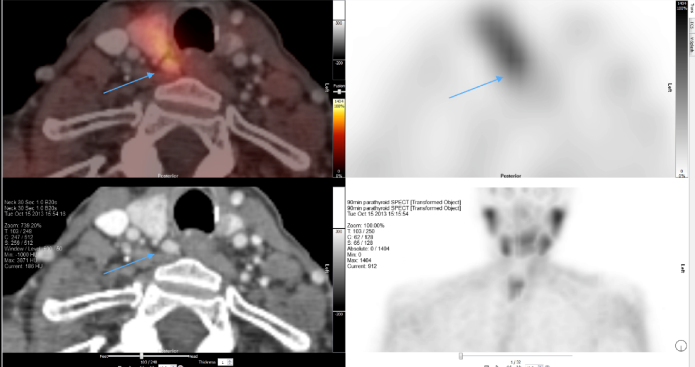

Sestamibi scan showing right sided parathyroid adenoma

Traditional parathyroid surgery with a large scar, division of muscles and the use of drains should almost never performed today. Parathyroid surgery therefore is at least by traditional standards now always minimally invasive, including when all 4 parathyroid glands need to be identified. The principle of parathyroid surgery has always been the identification of all parathyroid glands (the normal gland is no larger than half a grain of rice) and the removal of the parathyroid tumour. Whilst this is the gold standard operation there is a co-gold standard minimally invasive operation that relies on the pre-operative scans. Indeed when pre-operative scans unequivocally locate the disease the option of targeted surgery (with intraoperative PTH if required) is a co-gold standard operation with equivalent results. Reliable preoperative localisation studies including sestamibi scanning, high resolution ultrasound and 4D CT scanning permits the identification of the diseased parathyroid gland in the majority of cases, so most patients are candidates for a minimally invasive parathyroidectomy.

Many techniques of this minimal access parathyroidectomy exist including endoscopic parathyroidectomy, video-assisted parathyroidectomy, and mini incision parathyroidectomy under general or local anaesthesia. The principal advantage of the minimally invasive parathyroidectomy is that when performed appropriately it allows the parathyroid adenoma to be dissected and removed through a small incision, leaving the other neck tissues undisturbed. In the hands of specialist surgeons this technique offers results equivalent to the best traditional operation but with the added advantages of (i) a smaller incision, (ii) a shorter operation, (iii) shorter hospital stay and (iv) the possibility of a local rather than general anaesthetic. Intra-operatively it is now possible to measure the patient’s PTH level in addition when necessary to assess the parathyroid gland with the use of a microscope.